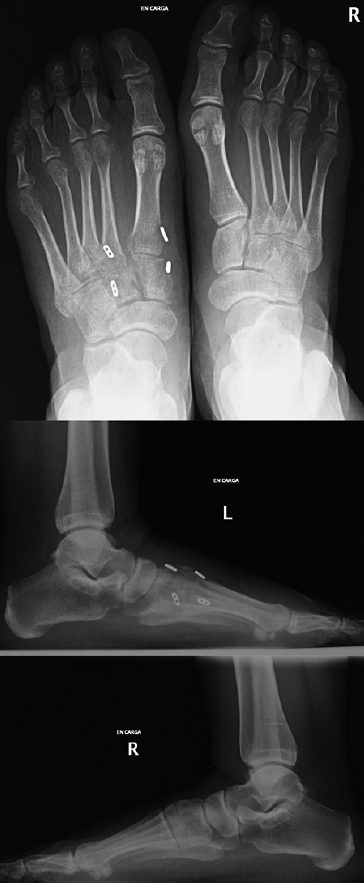

Figura 3. Caso 2. A: radiografía preoperatoria anteroposterior con diástasis en la articulación de Lisfranc; B: radiografía oblicua preoperatoria; C: corte de tomografía computarizada oblicuo.

Se trata de una mujer de 26 años atendida en urgencias tras un traumatismo con torsión del pie. Se realiza radiografía y TAC, objetivando diástasis de 9 mm sin lesión ósea (Figura 3) y diagnosticando, por tanto, lesión sutil de Lisfranc.